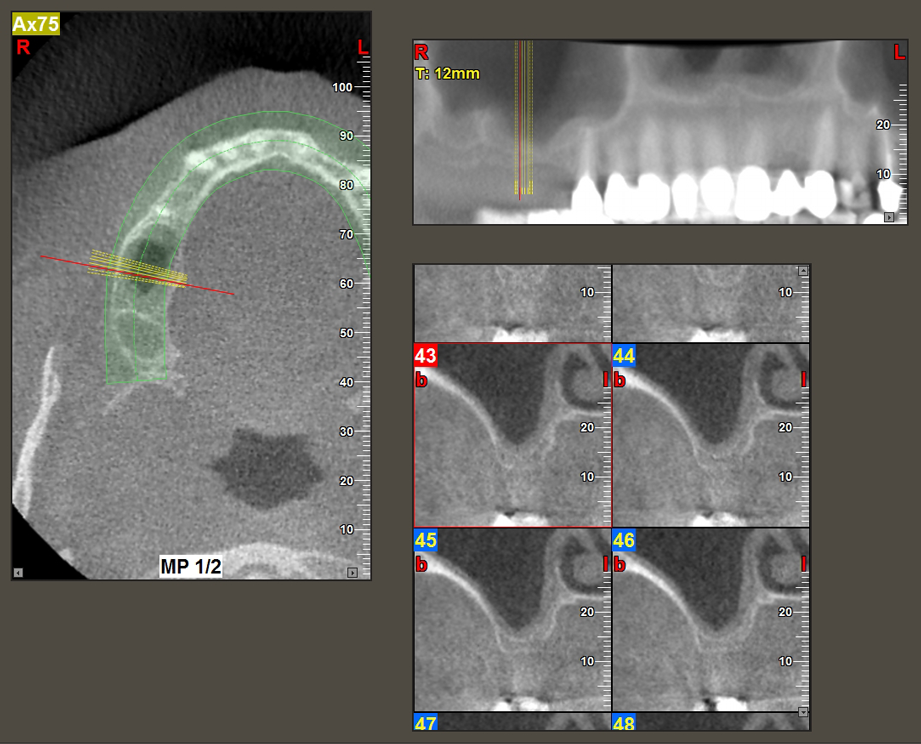

A 49-year-old female patient, a non-smoker and with nothing remarkable in her general medical history, was referred to our oral surgery practice for surgical extraction of tooth 16 and subsequent implantation. After the extraction, the patient experienced mild sinusitis trouble with the resultthat we initially waited six months before carrying out the measure. The residual bone height at the planned implant position measured 3-4 mm (Fig. 1 and 2).

The I2A instrument (diameter 2.0 mm) was then used to perforate the sinus floor intermittently and on the smallest scale possible. This special piezosurgical method ensures that the Schneiderian membrane is not damaged. When the Z25P was used, the membrane was already lifted slightly by the coolant supplied via the instrument tip (Fig. 3). The coolant quantity was just 50% in order to avoid high pressure in the implant bed.

Following an intermediate check (Fig. 4) a further preparation step was performed (Fig. 5). Afterwards, the hydraulic Z35P instrument was used to lift the membrane to the desired position (Fig. 6 and 7). This was followed by further piezosurgical preparation of the implant bed, concluded with a rotary bur and shoulder milling cutter up to the implant diameter of 4.8 mm. Before the implant was inserted, the augmentation material (particle size approx. 0.8-1.6 mm) was introduced underneath the Schneiderian membrane (Fig. 8).

To move the augmentation material in the direction of the maxillary sinus atraumatically, the implant was inserted very slowly by hand (Fig. 9). In the process, the membrane was pushed in the cranial direction once again. After two months, the surgical site healed without irritation. Six months later, the x-ray check showed a significant increase in opacity as an indication of ossification (Fig. 10). The prosthetic restoration was carried out with a metal-ceramic crown.